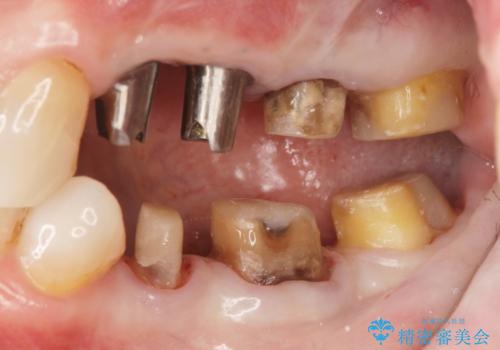

- 違和感や疼きのある左側小臼歯に加え全体的にクラウンや詰め物のやりかえを希望され来院されました。

治療後に再発した虫歯や根管再治療に加え、穴の空き症状のある上顎左側小臼歯は抜去を行いインプラントによる機能回復治療を計画します。

X線写真検査ではわからない虫歯も外してみると再発していることがあります。虫歯を丁寧に取り除き、再発を防ぐべく精密なクラウンの作製を行うことが長期的な予後につながります。